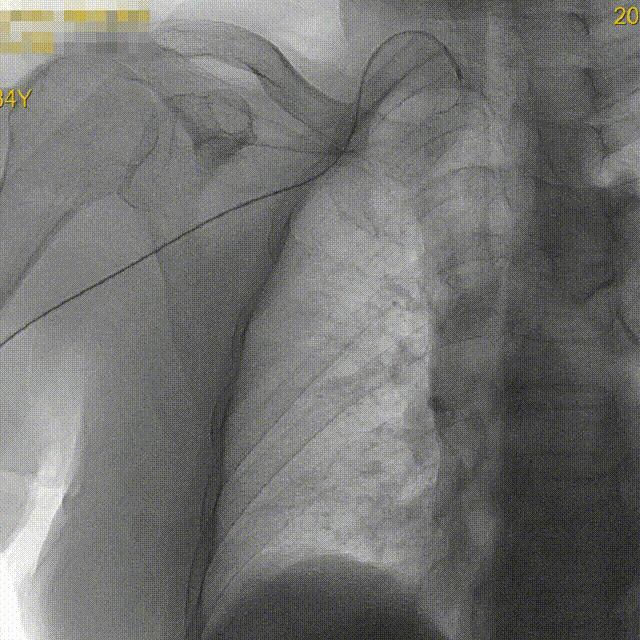

CTA提示右侧颈总动脉迂曲,右锁骨下动脉与右颈总动脉成钝角。